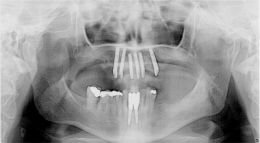

Il caso clinico che presentiamo si tratta di paziente sesso F anni 54, si presenta alla nostra osservazione mandata da altro collega, paziente con elementi dentali irrecuperabili dal punto di vista parodontale a livello dell’arcata superiore. Già eseguito visite in altro studio, il protocollo che era stato prospettato consisteva nell’avulsione di tutti gli elementi dentari dell’arcata superiore, un periodo di guarigione di circa quattro mesi, in questo periodo avrebbe dovuto portare una protesi amovibile con palato, dopo di che, inserimento di quattro impianti, ad avvenuta osteointegrazione circa cinque mesi successiva solidarizzazione con barra e protesi ancorata da attacchi. Abbiamo spiegato alla paziente che il protocollo era decisamente corretto,riabilitazioni di questo tipo hanno un follow up di molti anni. La paziente non voleva decisamente portare una protesi mobile. Abbiamo spiegato alla paziente che vi era anche un'altra possibilità, si trattava del carico immediato, la paziente molto motivata si era ripromessa di seguire tutte le indicazioni del caso. Non essendo possibile evitare contatti occlusali quando si riabilita un’intera arcata, il paziente deve essere istruito e utilizzare la protesi provvisoria fissa con moltissima attenzione, quindi la dieta per almeno due mesi deve essere morbida e liquida. Dopo attenta valutazione radiografica e tomografica, confezionamento di protesi armata in resina, si programma l’intervento.(foto 1,2,3,4,5,6,7,8,9) Avulsioni dentarie, incisione e scollamento del lembo, sottopreparazioni dei siti a 3,25 per inserire impianti Pitt Easy superficie purotex di diametro 3,75, tutti gli impianti vengono serrati a 40N.(foto 10,11) Vengono adattati abutment all’esterno del cavo orale, posizionati e serrati manualmente, ribasato provvisorio,rifinito e posizionato. La paziente viene dimessa con le terapie del caso.(12,13,14,15,16,17,18,19) L’intervento è iniziato alle 10,00 del mattino terminato alle ore 15,00 del pomeriggio. Molto importante in interventi di questo tipo è l’utilizzo di suture assorbibili in quanto il provvisorio non verrà rimosso prima di tre mesi. Il monitoraggio di tali pazienti deve essere continuo. (foto 20 otto giorni dall’intervento) A distanza di sei mesi altri due impianti sono stati inseriti in posizione 2,3 e 2,5. Sedi che in primo intervento si presentavano deficitarie, ma dopo rigenerazione ossea si è potuto intervenire. A distanza di altri sei mesi è stato applicata la protesi fissa in zirconio ceramica, il carico di questo lavoro ha un follow up di due anni. (foto 21,22,23) Da una attenta analisi della letteratura sul carico immediato di impianti endossei orali nell’uomo, si possono trarre alcune considerazioni. Possiamo notare per esempio che le prime sperimentazioni cliniche sul carico immediato sono state effettuate con overdenture mandibolari; queste, basandosi su un elevato numero di casi presi in considerazione (quasi 4000 impianti complessivamente inseriti in circa 1000 pazienti), hanno dimostrato una eccellente percentuale di successo a lungo termine. Successivamente il protocollo a carico immediato è stato utilizzato anche per le arcate complete fisse, soprattutto a livello mandibolare, raggiungendo percentuali di successo almeno pari se non addirittura superiori alle overdenture, considerando follow up fino a 10 anni. Invece per le riabilitazioni totali a livello dell’arcata superiore e altri tipi di costruzione protesica quali corone singole e protesi fisse monolaterali, sebbene i dati sinora disponibili forniscano risultati assai incoraggianti, è consigliabile attendere ulteriori evidenze scientifiche che dimostrino la reale predicibilità a lungo termine. Si può concludere che le riabilitazioni tipo over-denture e le arcate complete fisse a livello mandibolare rimangono a tutt’oggi le indicazioni più predicibili secondo i dati della letteratura e gli studi clinici condotti.